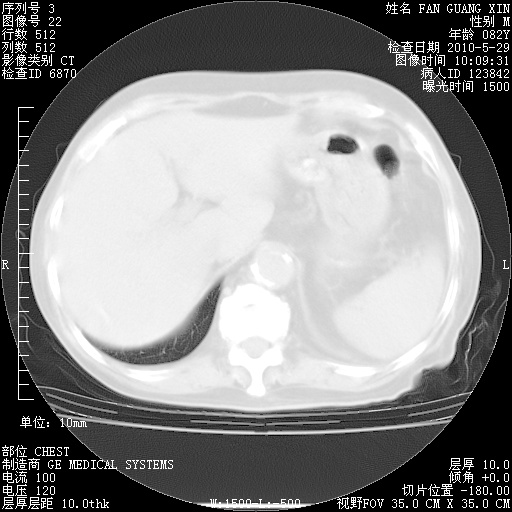

再治疗10天后的肺部CT

再治疗10天后的肺部CT 纵膈窗